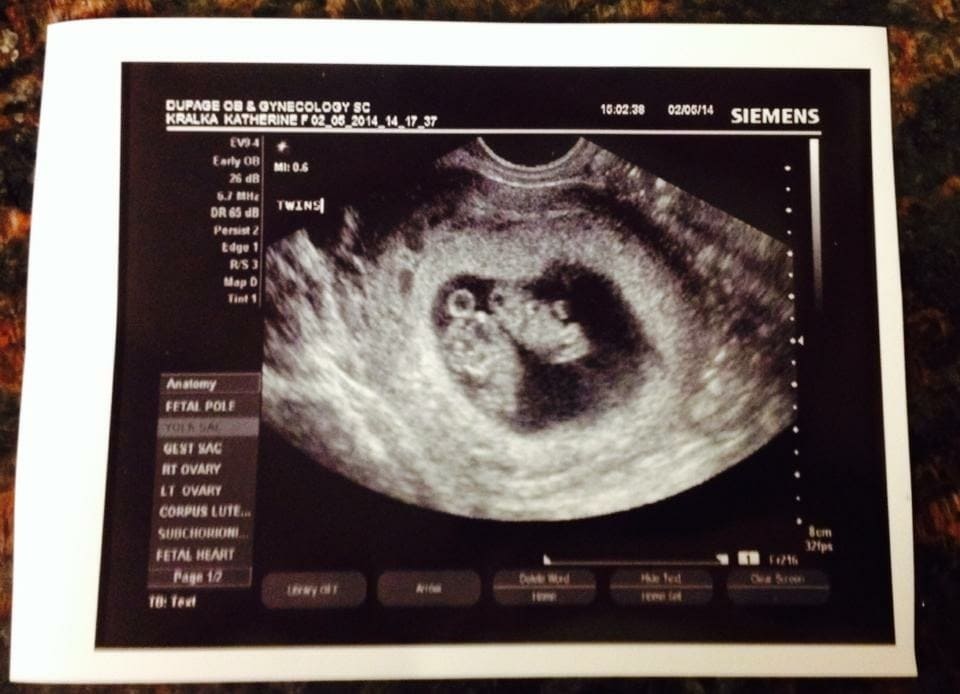

Ultrasound Photos of 9 Weeks Pregnant With Twins